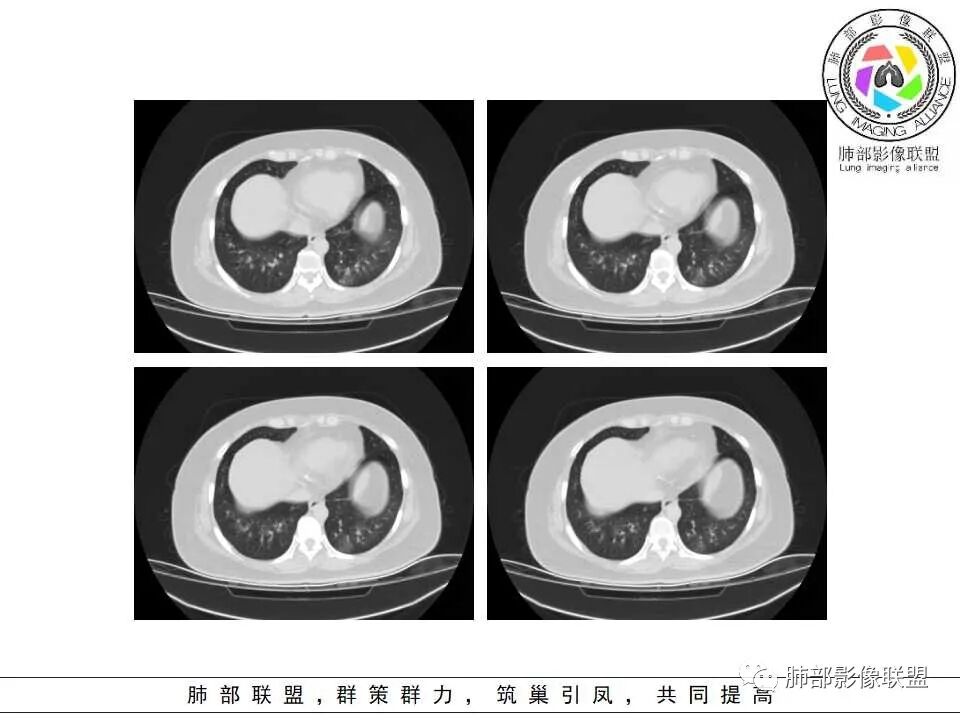

影像上是否有肺出血呀?感觉肺动脉周围有渗出,气道曲霉然后血管侵犯入血?

老年女性,发现白细胞升高两年,此次入院多次查外周血白细胞>30*10^9/L,淋巴降低,CRP显著升高,但病程中无发热,以细菌性炎不好解释;CT提示有脾大,结合外周血象,首先考虑存在血液系统疾病(白血病)基础,且未系统诊治;肺部CT提示双肺中轴间质增粗,伴随支气管管壁增厚?多发树丫及腺泡结节,部分呈点晕征,可见肺动脉分枝增粗,一元论考虑白血病肺部浸润;二院论考虑白血病并发气道侵袭曲霉。以患者病程进展看,更倾向于白血病肺部浸润。

肺动脉增粗,支气管有改变

肺动脉高压:性质待查,血象哪位老师解释一下,看右上支气管,怀疑以前都有过

二.血管侵袭性肺曲霉病

1.多见于血液恶性肿瘤及造血干细胞移植患者。两肺多发,多见磨玻璃晕,有时病灶基底贴近胸壁形成楔形影。

2.很少支气管壁增厚,也无支气管扩张,少见树芽征。